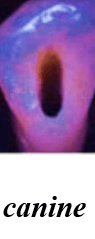

Shapes of the access cavity of all teeth

| Tooth | Access cavity shape | Average depth |

|---|---|---|

| Maxillary incisors | Triangular or oval (placed over the palatal surface) |

3-4 mm |

| Mandibular incisors | Triangular (placed over the lingual surface)

|

3-4 mm |

| Maxillary canines | Oval (placed over the palatal surface)

|

4-5 mm |

| Mandibular canines | Oval (placed over the lingual surface)

|

4-5 mm |

| Maxillary premolars | Oval or rounded (located over central part of the tooth)

|

4-5 mm |

| Mandibular premolars | Oval (over central of the tooth, slightly to the lingual)

|

4-5 mm |

| Maxillary molars | Trapezoidal (located over the mesial buccal cusp or the central part of the tooth)

|

5-6 mm |

| Mandibular molars | Trapezoidal or rhomboidal (centered over the mesial buccal cusp)

|

5-6 mm |

| Maxillary second molars | Trapezoidal (centered more mesially and palatally, slightly off-center) | 5-6 mm |

| Mandibular second molars | Trapezoidal or rhomboidal (centered over the mesial buccal cusp) | 5-6 mm |

| Maxillary third molars | Oval or trapezoidal | 5-7 mm |

| Mandibular third molars | Trapezoidal | 5-7 mm |